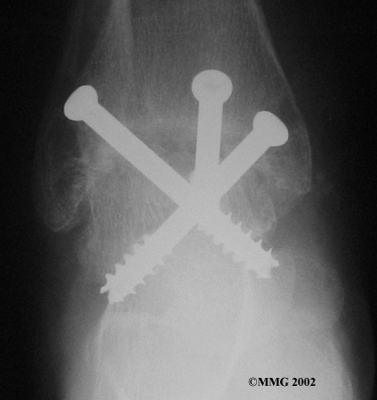

Ankle Fusion

When the ankle joint becomes so painful that it is difficult to walk, surgery may be suggested to fuse the ankle joint. An ankle fusion is sometimes also called an ankle arthrodesis. In this operation, the three bones that make up the ankle joint (the talus, the tibia, and the fibula) are allowed to grow together, or fuse, into one bone. Once this is done the ankle no longer is able to move, but with a successful fusion the pain is gone. Most people with a successful fusion of the ankle are able to walk without much trouble, and in some cases it is almost impossible to tell that the ankle is stiff. But it is very difficult to run because you lose the ability to push off with the toes. The foot can't bend down.

Ankle Fusion

Most people will need some changes made to their shoes following an ankle fusion. Because the ankle no longer moves, it is difficult to roll over the top of the foot when you take a step. For this reason, shoes are usually fitted with a rocker sole. This allows the shoe to roll instead of the foot. A special heel is sometimes built on the shoe to absorb some of the shock.

The ankle fusion is a good operation, especially for a young, active person. It is usually the preferred option for post-traumatic arthritis of the ankle. Once the ankle is successfully fused it can last a lifetime, and no other operations are expected later unless there are problems. But there are complications associated with the ankle fusion, and not all ankle fusions are successful.